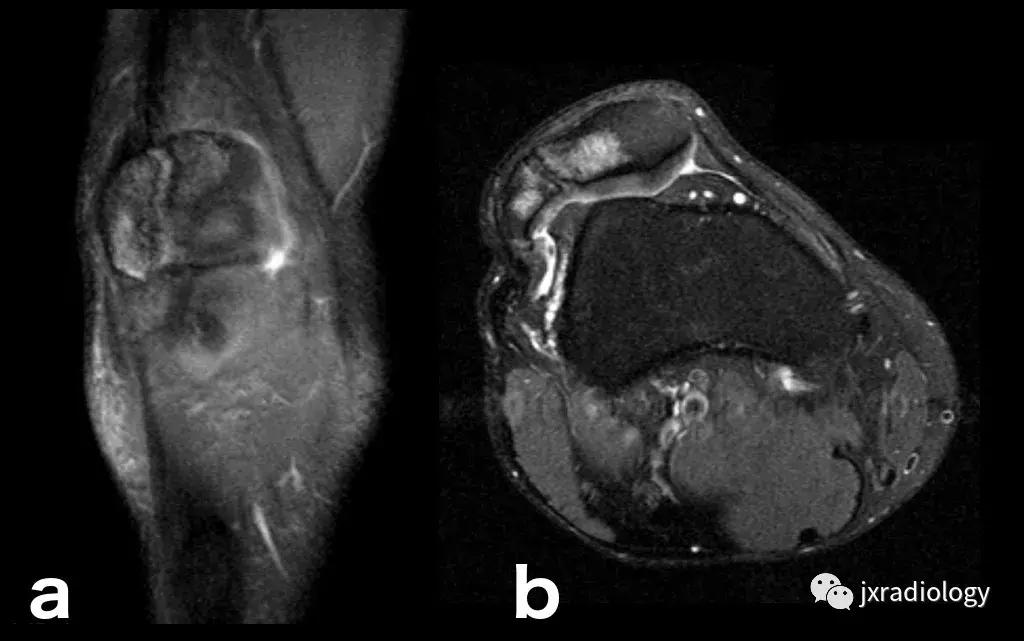

图22:骨肉瘤(a,b:冠状和轴向PD-FS-WI):肿瘤性水肿继发于骨小梁破坏引起的直接毛细血管损伤,并伴有血管内液体释放和出血。区分周围水肿和肿瘤侵袭可能是困难的。

图23:骨巨细胞瘤(PD-FS-WI):也存在肿瘤性骨髓水肿。